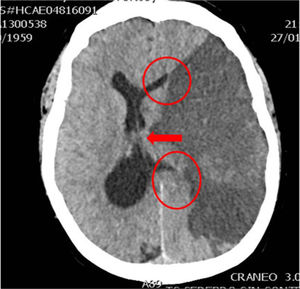

En la práctica clínica, antes de establecer un pronóstico definitivo, se recomienda la opinión de un equipo multidisciplinar experto, que minimice el sesgo personal; en esta valoración el especialista en Medicina Intensiva, por sus conocimientos sobre la enfermedad neurocrítica, juega un papel primordial. La lesión cerebral catastrófica condiciona una elevada presión intracraneal (PIC), con una disminución de la presión de perfusión cerebral e instauración progresiva de la parada circulatoria cerebral. La probabilidad de evolucionar a ME ha de sustentarse en datos clínicos, de neuromonitorización y resultados de la tomografía computarizada (TC) craneal. En primer lugar, hay que tener en cuenta la situación clínica neurológica, medida por las escalas habituales de gravedad según las diferentes enfermedades (escalas de Glasgow [GCS], Hunt y Hess, NIHSS), así como la ausencia de algunos reflejos de tronco del encéfalo. Las escalas de gravedad realizadas en las primeras horas de la lesión tienen sus limitaciones y su valor pronóstico mejora cuando se realizan después de la reanimación del paciente. La probabilidad de error pronóstico es siempre menor cuando estas escalas tienen un valor extremo; a mayor gravedad clínica, mayor probabilidad de evolución a ME37. En este sentido, algunos estudios encuentran que la abolición de 3 reflejos de tronco al ingreso es la variable que más predice la evolución a ME38. Otro de los factores pronósticos que pueden ayudar a predecir una alta probabilidad de evolución a ME es la TC craneal, ya que permite documentar el tipo, el volumen, la localización y la gravedad de la lesión estructural, así como la existencia de signos de hipertensión intracraneal y herniación cerebral. En las hemorragias cerebrales, el volumen del hematoma es uno de los predictores más potentes de evolución a ME y algunos autores encuentran que un volumen superior a 65cc es un factor determinante39. Igualmente, la presencia del «signo del remolino» en la TC sin contraste y del spot sign en la angio-TC nos indica que hay presencia de sangrado activo por arteriolas o vénulas y es un signo de mal pronóstico que algunos autores asocian con una mayor probabilidad de evolución a ME38,40,41. El desplazamiento de la línea media nos informa del grado de compresión y es un indicador, junto con el estado de las cisternas de la base, del compromiso de las estructuras encefálicas. El borramiento parcial o total de las cisternas de la base es un fuerte indicador de probable evolución a ME42. La presencia de signos de herniación cerebral en la TC implica hipertensión intracraneal y, por lo tanto, riesgo elevado de enclavamiento cerebral. Los 3 tipos más frecuentes de herniación cerebral son: herniación subfalcial, que se caracteriza por un desplazamiento de la línea media y compresión del ventrículo lateral ipsilateral (fig. 1), la herniación uncal o transtentorial, donde existe una dilatación de la cisterna del ángulo pontocerebeloso ipsilateral y del cuerno temporal del ventrículo lateral contralateral (fig. 2), y la herniación amigdalina, que se caracteriza por la desaparición de la cisterna magna y el descenso de las amígdalas cerebelosas por debajo de la línea de Chamberlain. La vaina del nervio óptico se continúa con las meninges del sistema nervioso central y acumula líquido cefalorraquídeo en este espacio subaracnoideo, aumentando su diámetro cuando hay un incremento de la PIC. Su diámetro se puede medir por ultrasonidos, resonancia magnética y TC craneal, y aunque no existe unanimidad sobre el lugar de la medición ni el diámetro necesario para considerar hipertensión intracraneal, algunos autores confirman que un diámetro de la vaina del nervio óptico>5-6mm tiene una fuerte correlación con una PIC superior a 20mmHg43,44.

Caso 1Varón de 76 años con HTA, sin otros antecedentes de interés. Deterioro brusco del nivel de consciencia en su domicilio con un GSC de 4 (O1, V1, M2). Se activa código ictus y es intubado por el servicio de emergencias extrahospitalario. Al ingreso en el hospital, la TC craneal muestra hemorragia masiva de ganglios de la base izquierdos abierta a ventrículos, importante edema cerebral y signos de herniación cerebral (fig. 4). Valorado por el Servicio de Neurocirugía y UCI, ante la situación clínica y los hallazgos de la TC craneal, se descarta cualquier tipo de tratamiento. No existe documento de voluntades anticipadas. Se informa a la familia y se realiza la entrevista previa en el Servicio de Urgencias, aceptando el ingreso en la UCI con la exclusiva finalidad de la donación de órganos. Evolución a ME en 28h, siendo donante de hígado. El receptor hepático presentó buena evolución, siendo dado de alta de la UCI en el cuarto día postrasplante.

Caso 3Varón de 79 años con pérdida brusca de consciencia en su domicilio. Los servicios de emergencia objetivan un GCS de 4 (O1, V1, M2), pupilas arreactivas y presión arterial de 205/115mmHg. Se procede a realizar intubación traqueal y traslado al hospital; en Urgencias obtiene un GSC de 4 y ausencia de reflejos fotomotor, corneal y oculocefálico. La TC craneal mostró un hematoma intraparenquimatoso en los ganglios de la base derechos, desplazamiento de la línea media e invasión del sistema ventricular (fig. 6). Valorado por Neurocirugía y Neurología, se descartó cualquier tipo de tratamiento. El CT planteó a la familia la posibilidad de la donación de órganos, aceptando esta el ingreso en la UCI para facilitar la donación en ME. A las 48h el paciente se mantenía en coma arreactivo, sin reflejos fotomotor, corneal ni oculocefálicos, pero con persistencia del reflejo tusígeno y de respiración espontánea. La familia no deseaba prolongar más la situación, por lo que se decidió la retirada del soporte ventilatorio. Se les planteó entonces la opción de la donación en asistolia controlada, que autorizaron. Se realizó extracción de riñones y córneas. Los riñones fueron trasplantados, presentando función renal inmediata y buena evolución posterior.